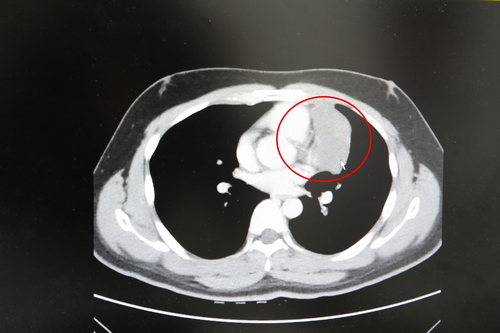

張睿智主任表示,經過電腦斷層掃描後,陳先生的腫瘤為八公分大的胸腺瘤,形狀如雞蛋,不僅離心包膜、血管非常近,執行手術有一定的難度,所以使用達文西手術為陳先生移除腫瘤過程中須小心翼翼地先將前縱膈腔的腫瘤與血管分離,再將腫瘤完整清除乾淨。

紅圈處為陳先生的胸腺瘤,已有八公分大,腫瘤非常靠近心包膜與血管  紅圈處為陳先生的胸腺瘤,已有八公分大,腫瘤非常靠近心包膜與血管